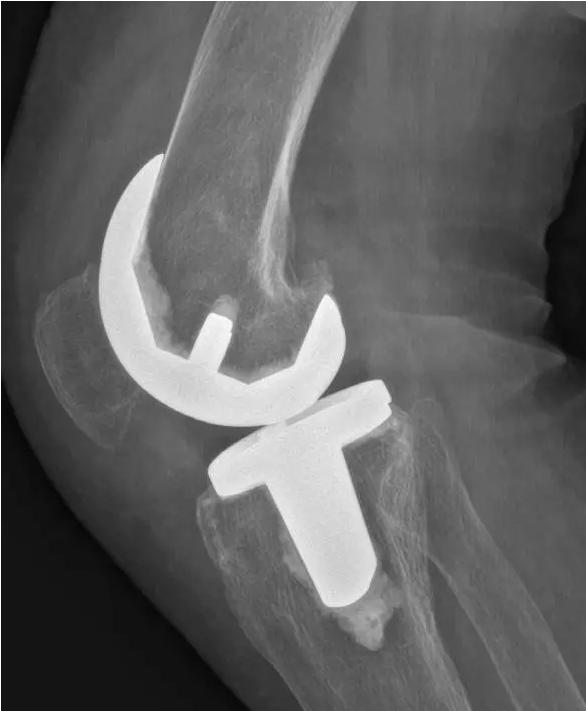

术后图如下:

对于晚期(重度)骨关节炎,保守治疗无效时,要积极考虑手术治疗。目前效果最佳的手术方式即为关节置换手术,其他手术方式如关节融合手术等效果较关节置换术相差较大,已不在临床广泛使用。关节置换手术的目的是缓解患者疼痛,矫正关节畸形,恢复关节功能,恢复正常生活。对于老年人来说,积极的手术治疗可以有效恢复其日常生活,避免因疼痛及活动障碍导致患者扶拐或坐轮椅,有效减少因缺乏运动导致的心肺功能障碍及精神问题发生。经过几十年的发展,目前关节置换技术已十分成熟,临床上目前采用的微创技术,手术创伤小,术中出血非常少,术后第二天患者即可下地行走,三月之后即可恢复正常生活及功能。至于人工假体使用寿命,目前进口关节多为20-30年,能满足60-70岁患者的需求。需要注意的是,在行关节置换手术之后,患者仍需要进行积极的康复治疗,包括关节活动度及周围肌力的锻炼等,这样才能达到最佳的手术效果。